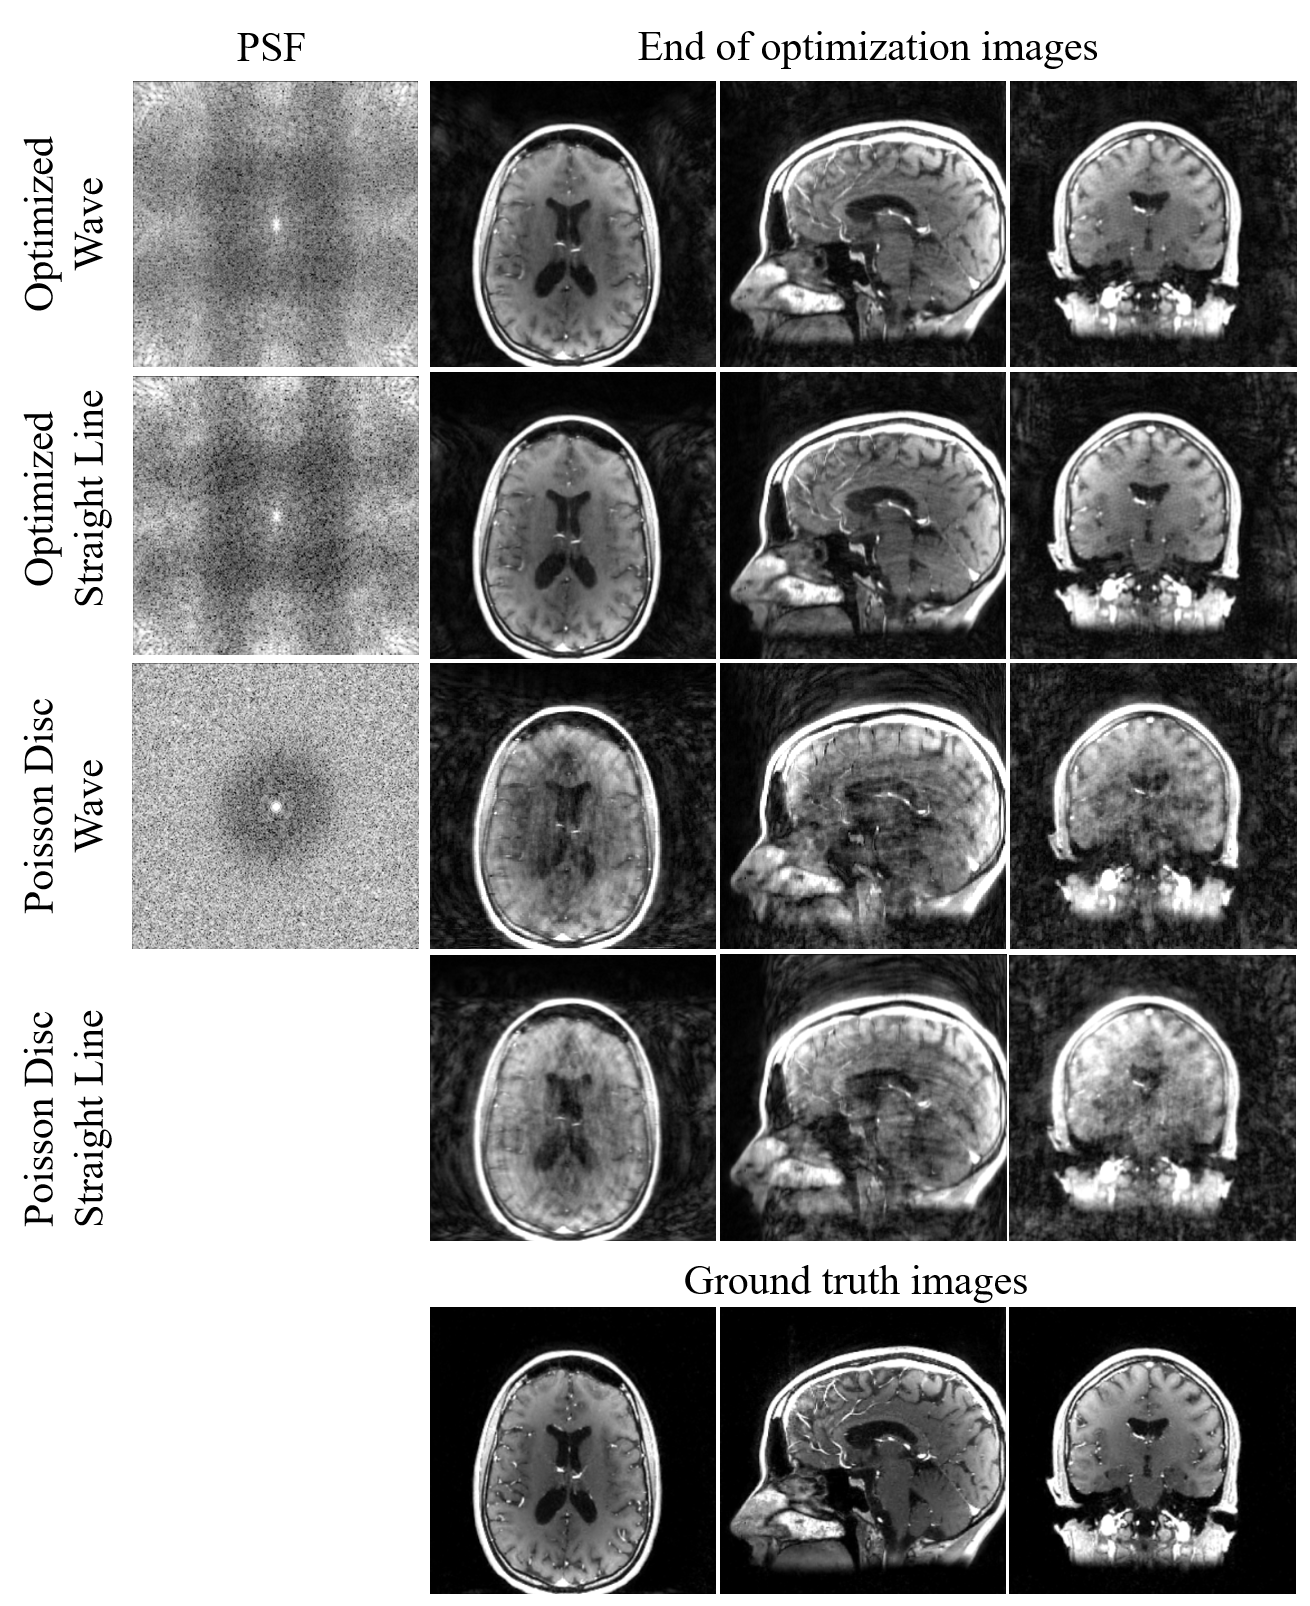

Shown in Figure 3 are the PSF of the optimized patterns and the simulated reconstructed images. Images sampled with the wave trajectory show less aliasing artifacts and closest to ground truths.

Figure 3. Left column: Point spread function (PSF) in logarithmic scale for various trajectories. Right columns: top to bottom: inverse NUFFT and coil combined images sampled with optimized wave trajectories, optimized straight line readout trajectories, and the initial Poisson disc with and without wave readout. The optimized wave trajectory shows a well-behaved PSF and the highest image quality.